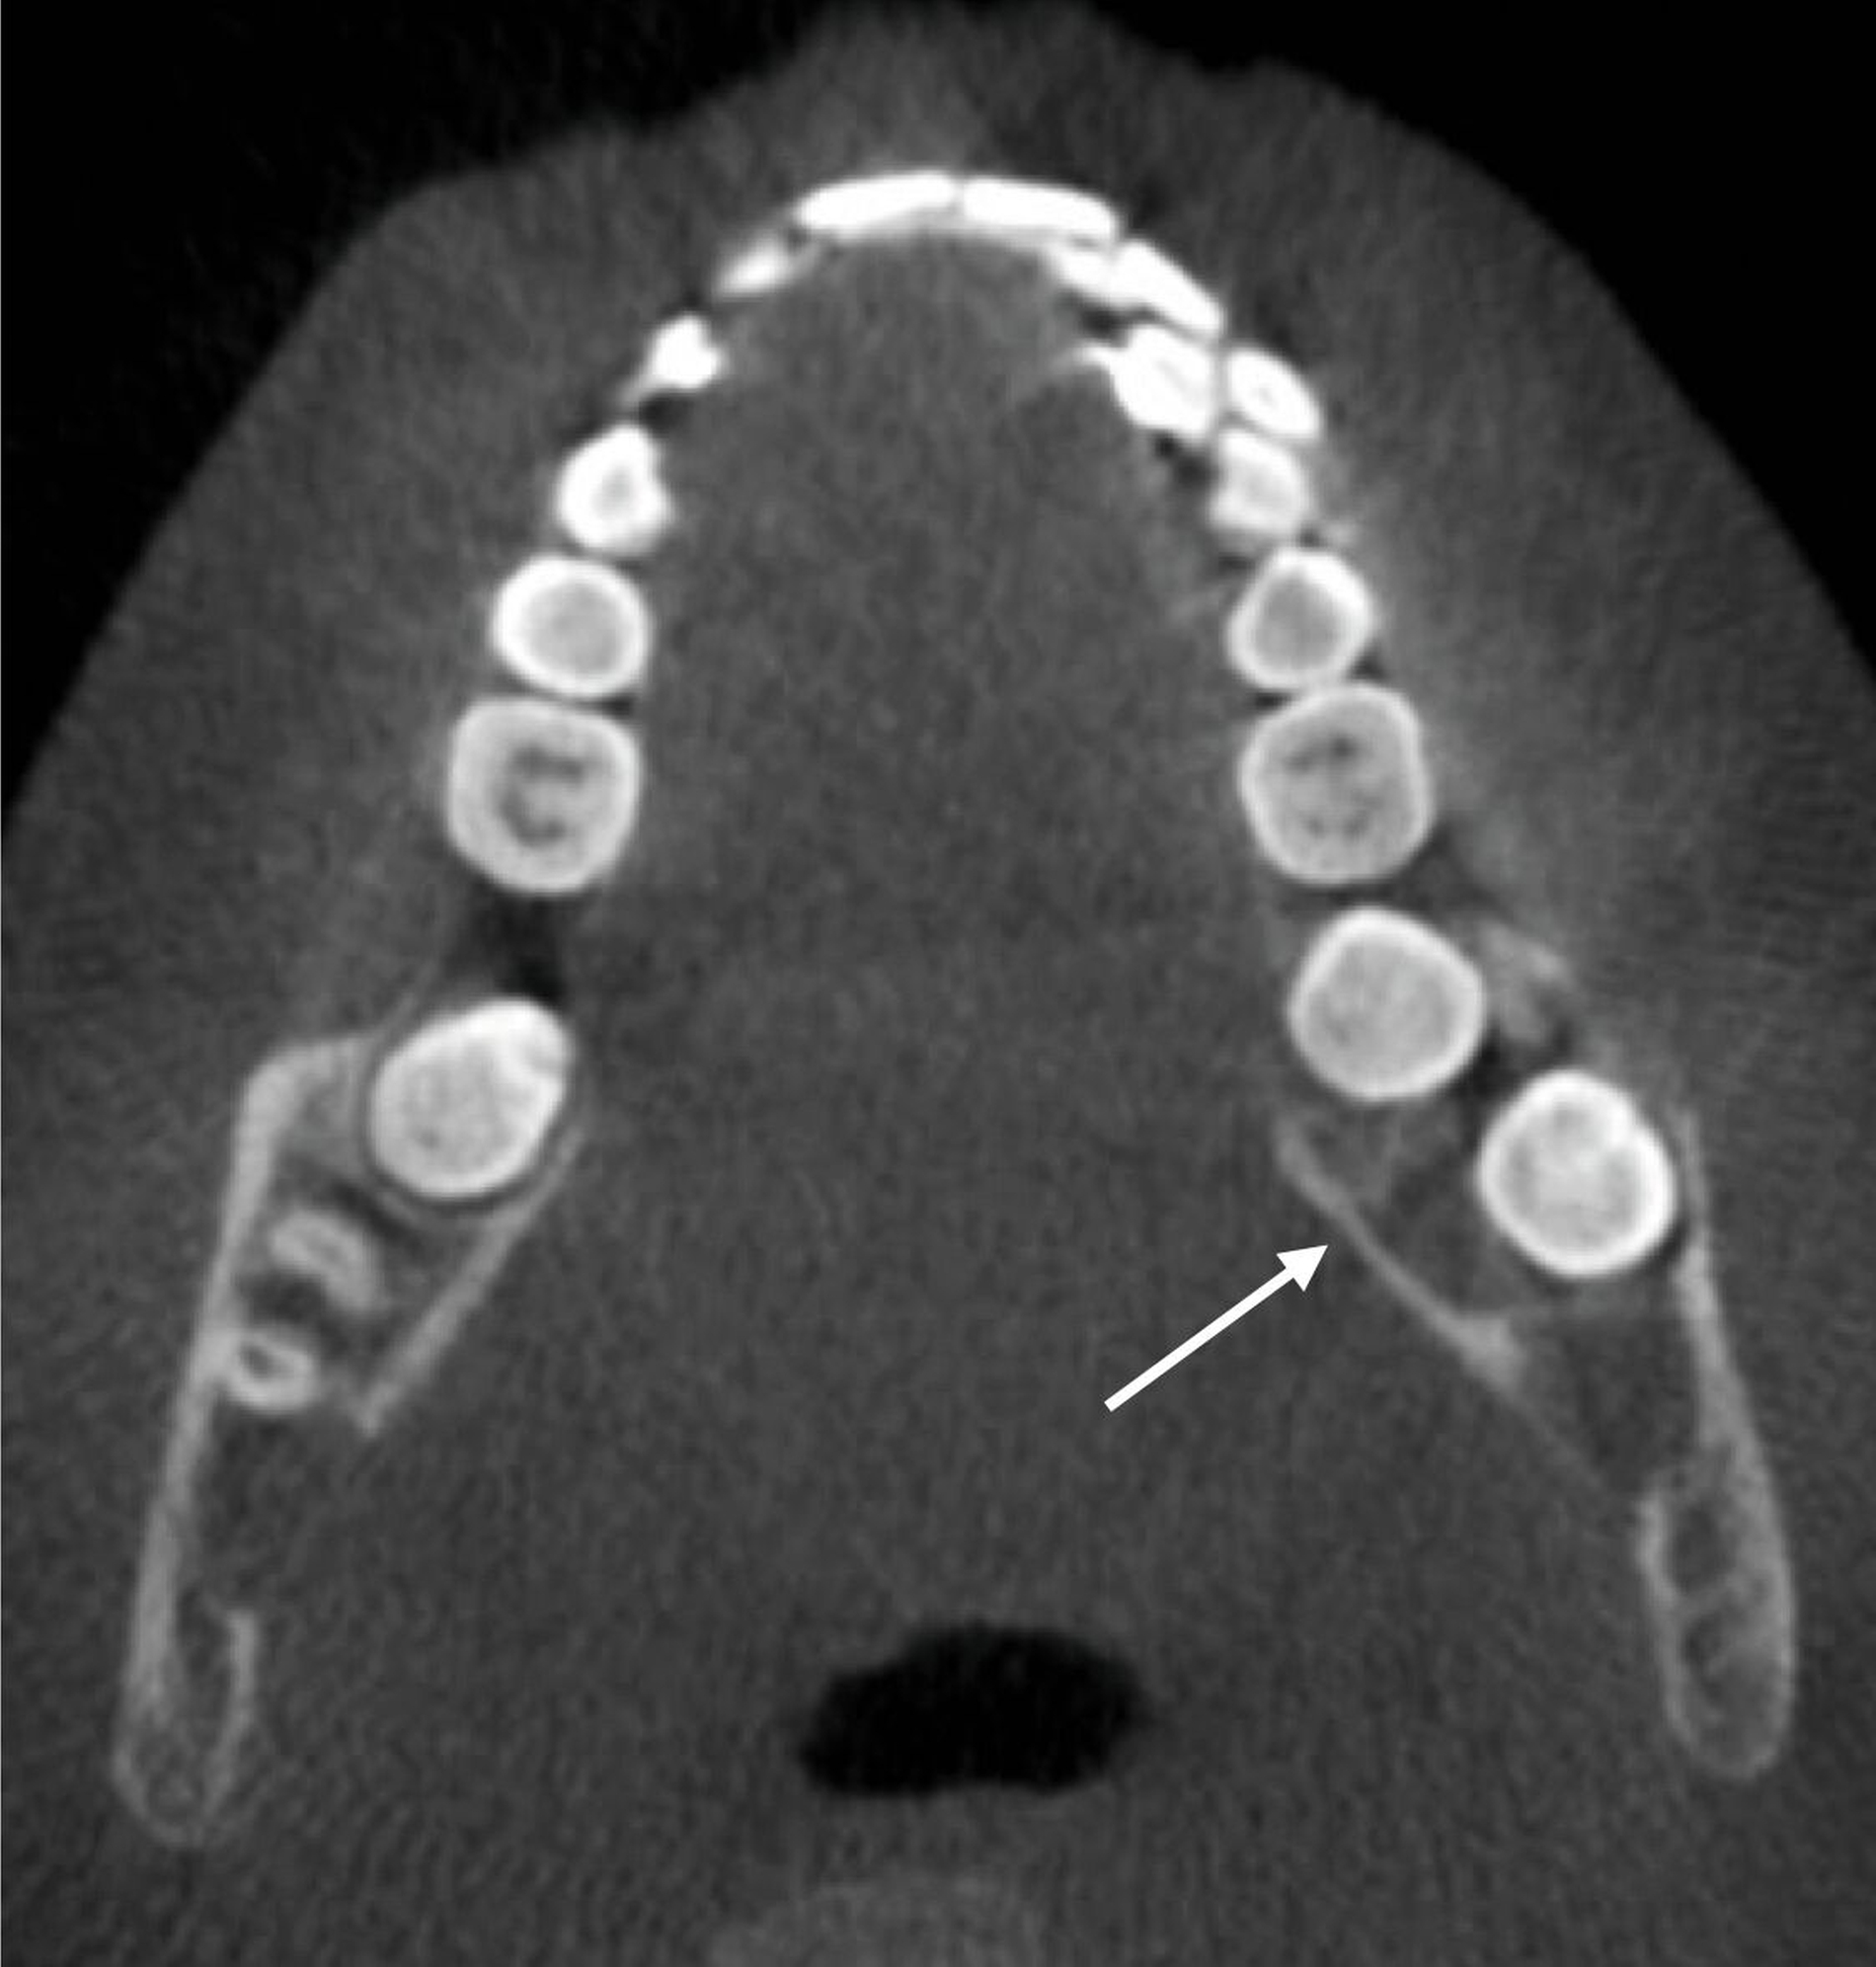

Ein 16-jähriger Junge stellte sich nach Überweisung durch seine behandelnde Kieferorthopädin aufgrund einer progredienten Schwellung des linken Unterkiefers in der Klinik und Poliklinik für Mund-, Kiefer- und Gesichtschirurgie vor. In der klinischen Untersuchung zeigte sich ein prominenter Befund distal der Zahnreihe mit hyperplastisch wirkender Schleimhaut (Abbildung 1).

Um diese Befunde bezüglich ihrer Lage und ihrer Ausdehnung genauer zu charakterisieren, erfolgte anschließend eine dreidimensionale Aufnahme in Form einer Digitalen Volumentomografie. In dieser ließen sich analog zu den Befunden in der zweidimensionalen Bildgebung gelappte hypodense Raumforderungen darstellen. Der sklerotische Randsaum und die – im Vergleich zur Spongiosa – hypodensere Struktur des Befunds im dritten Quadranten waren klar zu erkennen (Abbildung 3).